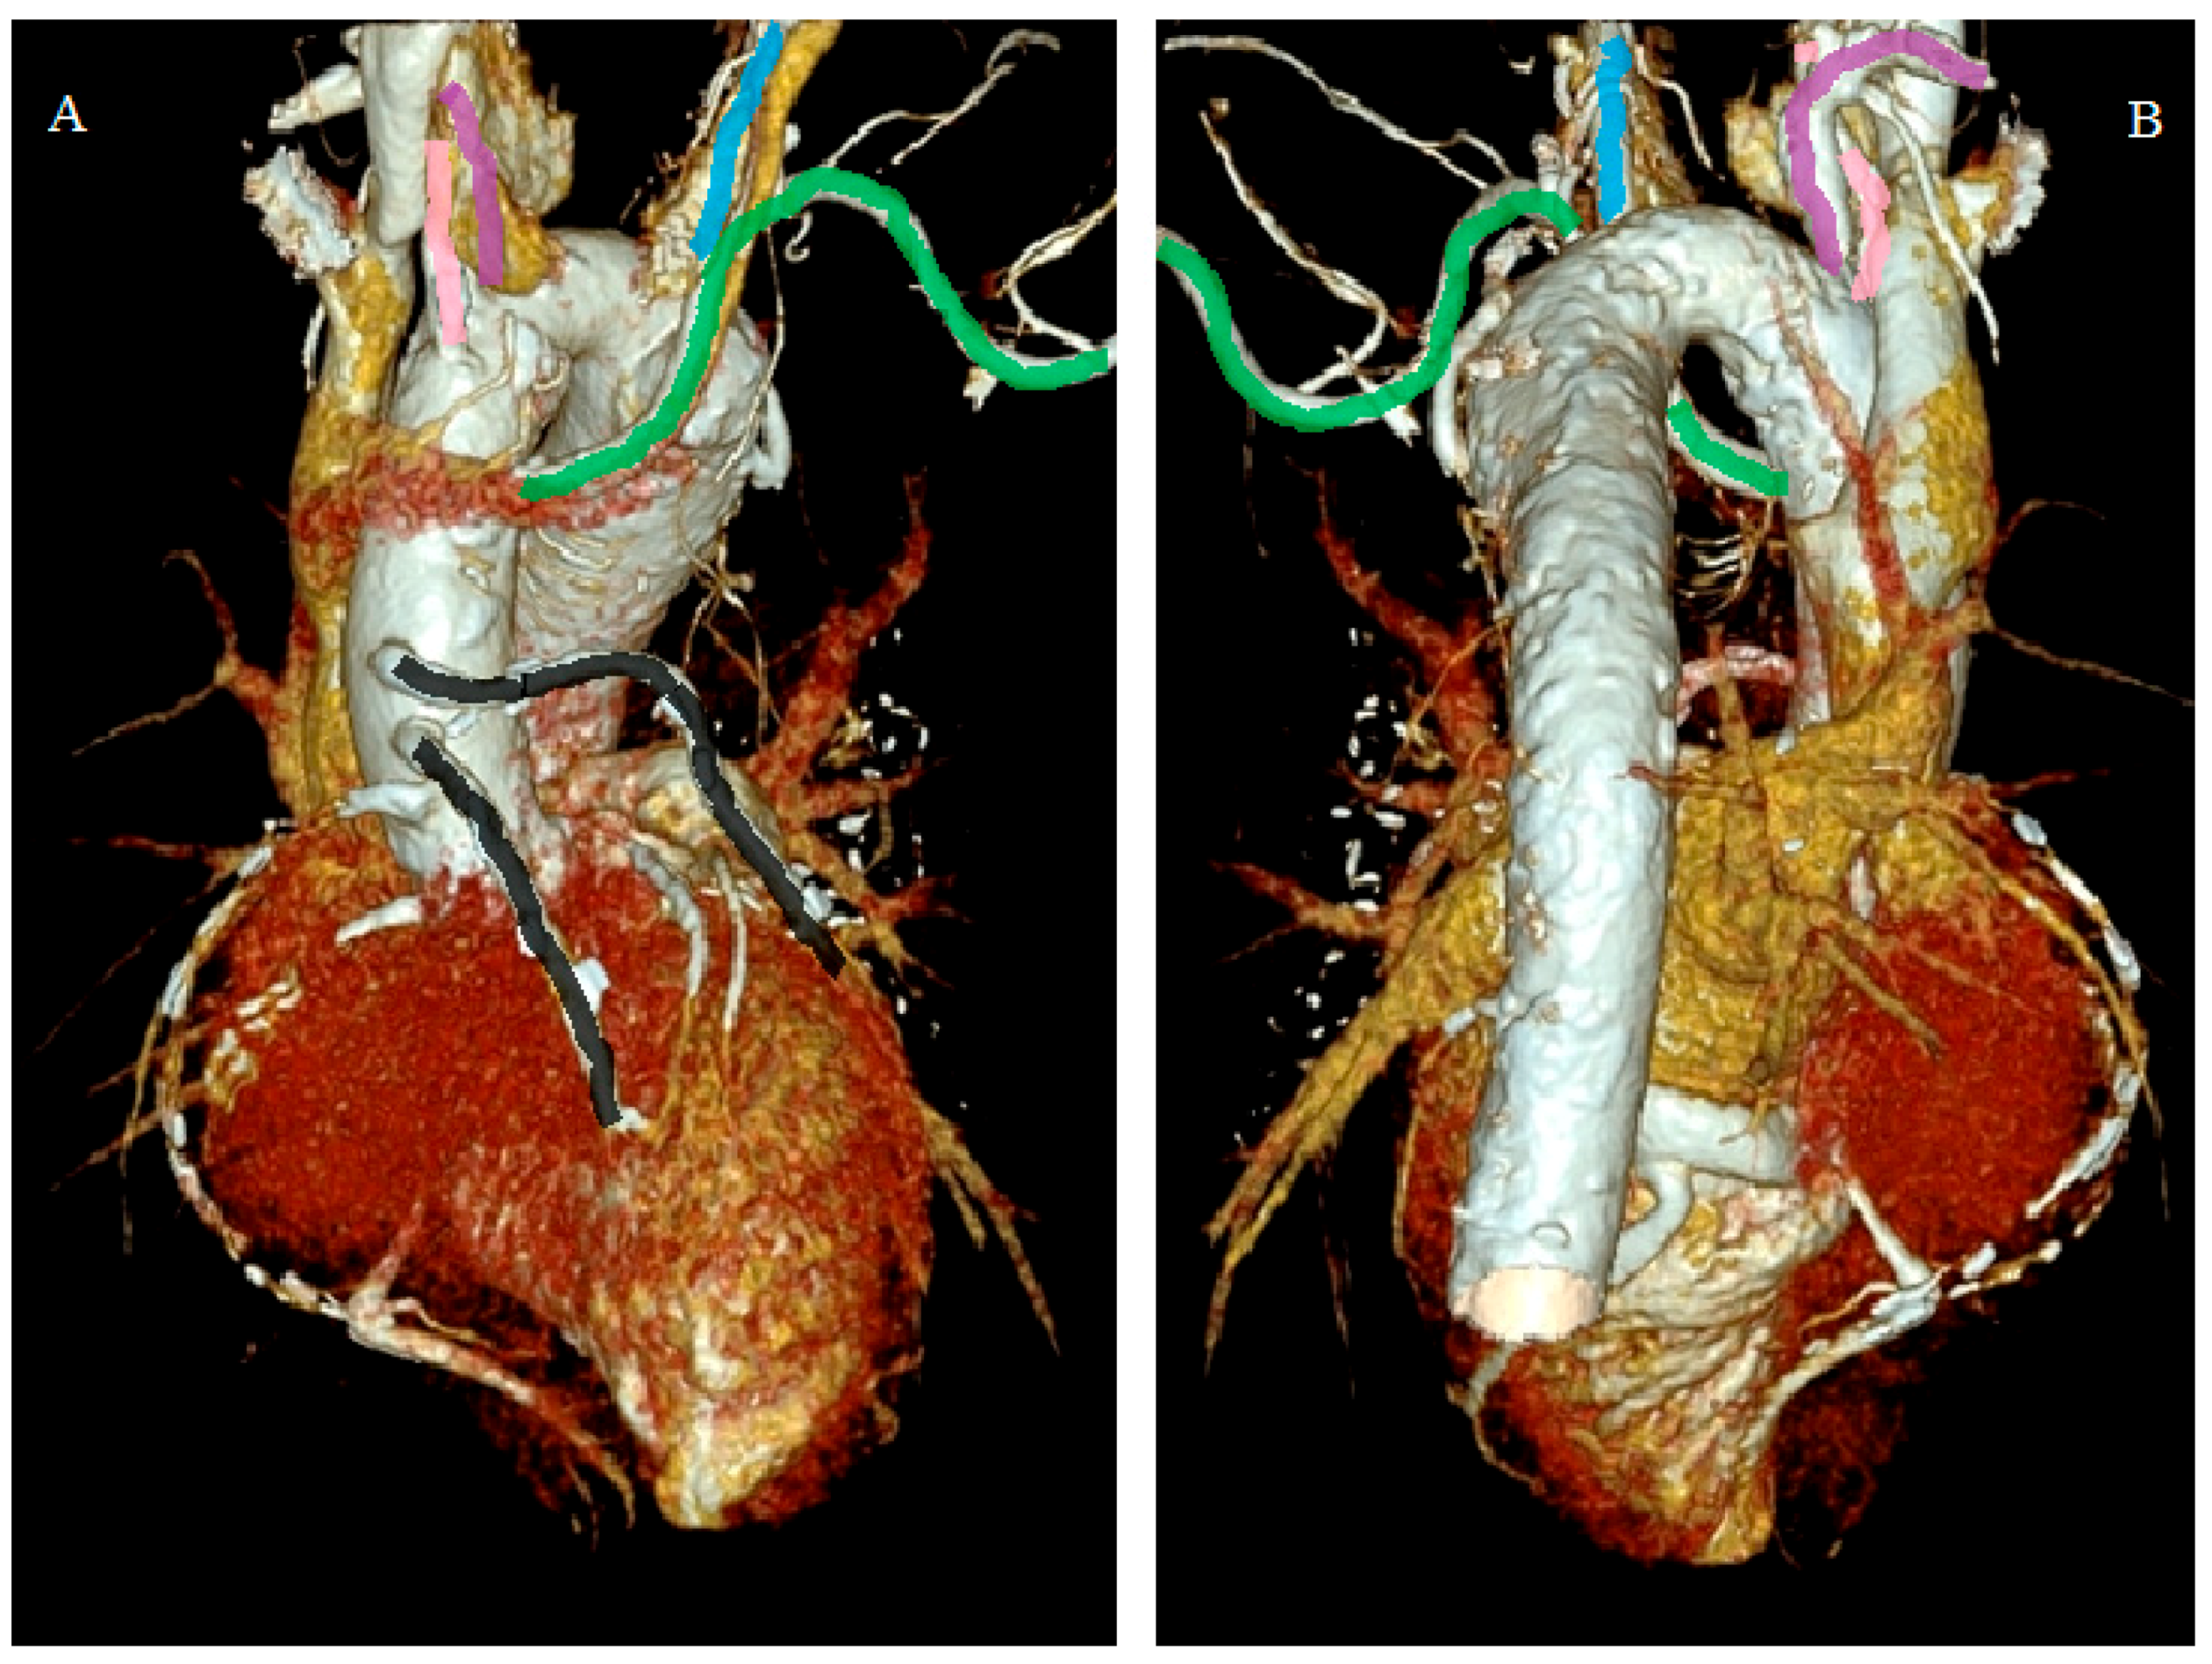

- Incidental vascular finding No. 2: Right Aortic Arch.